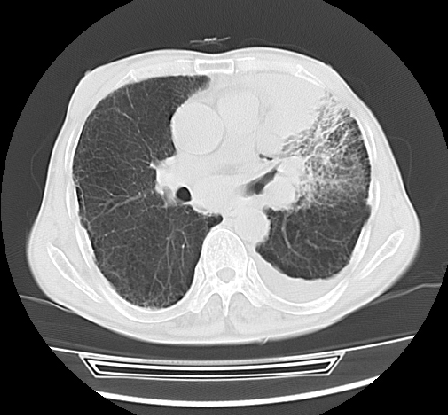

以下是引用ct诊断高手在2009-5-29 13:50:00的发言:[br]考虑左侧中央型肺癌,阻塞性肺炎伴肺不张。纵隔淋巴结转移。慢支 肺间质纤维化肺气肿。左侧胸腔积液。左侧肋骨转移?

以下是引用hhcckk在2009-5-29 14:58:00的发言:[br]左上周围型肺癌,左肺门、纵隔淋巴结转移,左侧胸腔积液,左侧肋骨转移[br]